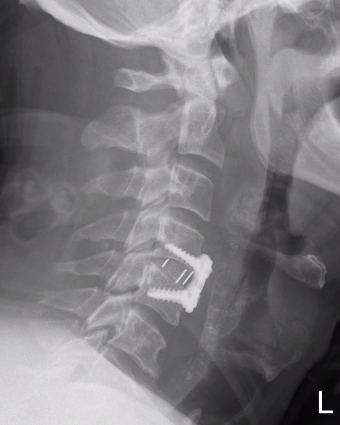

Xray / CT

Large antero-inferior body fragment / tear drop

- > 20 %

- stays attached to ALL

+/- posterior superior fragment retropulsed into canal